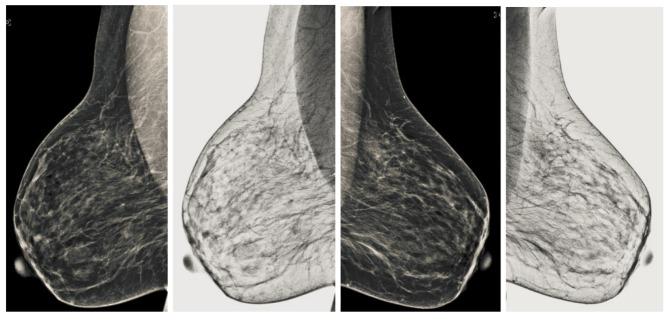

Breast cancer is widespread around the world and can be cured if diagnosed at an early stage. Digital mammograms are used as the most effective imaging modalities for the diagnosis of breast cancer. However, mammography images suffer from low contrast, background noise as well as contrast as non-coherency among the regions, and these factors makes breast cancer diagnosis challenging. These problems can be overcome by using a new image enhancement technique. The objective of this research work is to enhance mammography images to improve the overall process of segmentation and classification of breast cancer diagnosis. We proposed the image enhancement for mammogram images, as well as the ablation of the pectoral muscle. The image enhancement technique involves several steps. In the first step, we process the mammography images in three channels (red, green and blue), the second step is based on the uniformity of the background on morphological operations, and the third step is to obtain a well-contrasted image using principal component analysis (PCA). The fourth step is based on the removal of the pectoral muscle using a seed-based region growth technique, and the last step contains the coherence of the different regions of the image using a second order Gaussian Laplacian (LoG) and an oriented diffusion filter to obtain a much-improved contrast image. The proposed image enhancement technique is tested with our data collected from different hospitals in Qassim health cluster Qassim province Saudi Arabia, and it contains the five Breast Imaging and Reporting System (BI-RADS) categories and this database contained 11,194 images (the images contain carnio-caudal (CC) view and mediolateral oblique(MLO) view of mammography images), and we used approximately 700 images to validate our database. We have achieved improved performance in terms of peak signal-to-noise ratio, contrast, and effective measurement of enhancement (EME) as well as our proposed image enhancement technique outperforms existing image enhancement methods. This performance of our proposed method demonstrates the ability to improve the diagnostic performance of the computerized breast cancer detection method.